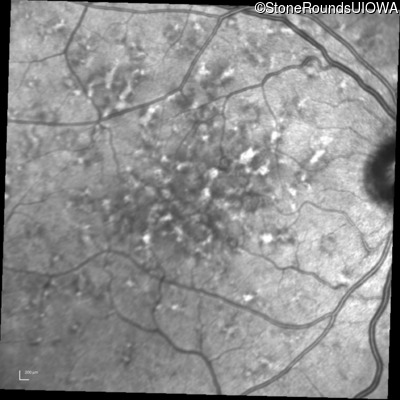

Blue Autofluorescence - Left - 20/32 sc

Exemplar